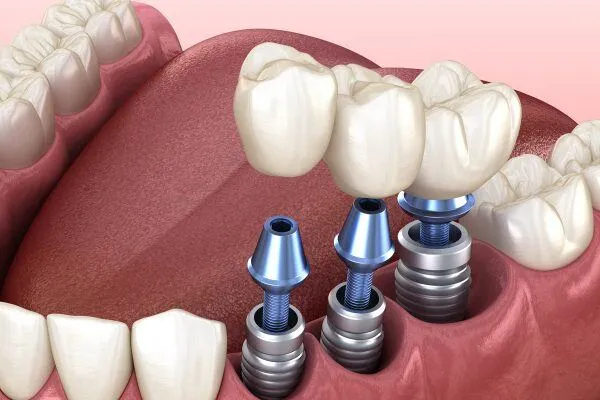

Trồng răng implant có đau không là câu hỏi mà các bác sĩ nha khoa thường xuyên nhận được. Câu trả lời ngắn gọn là: không đau,